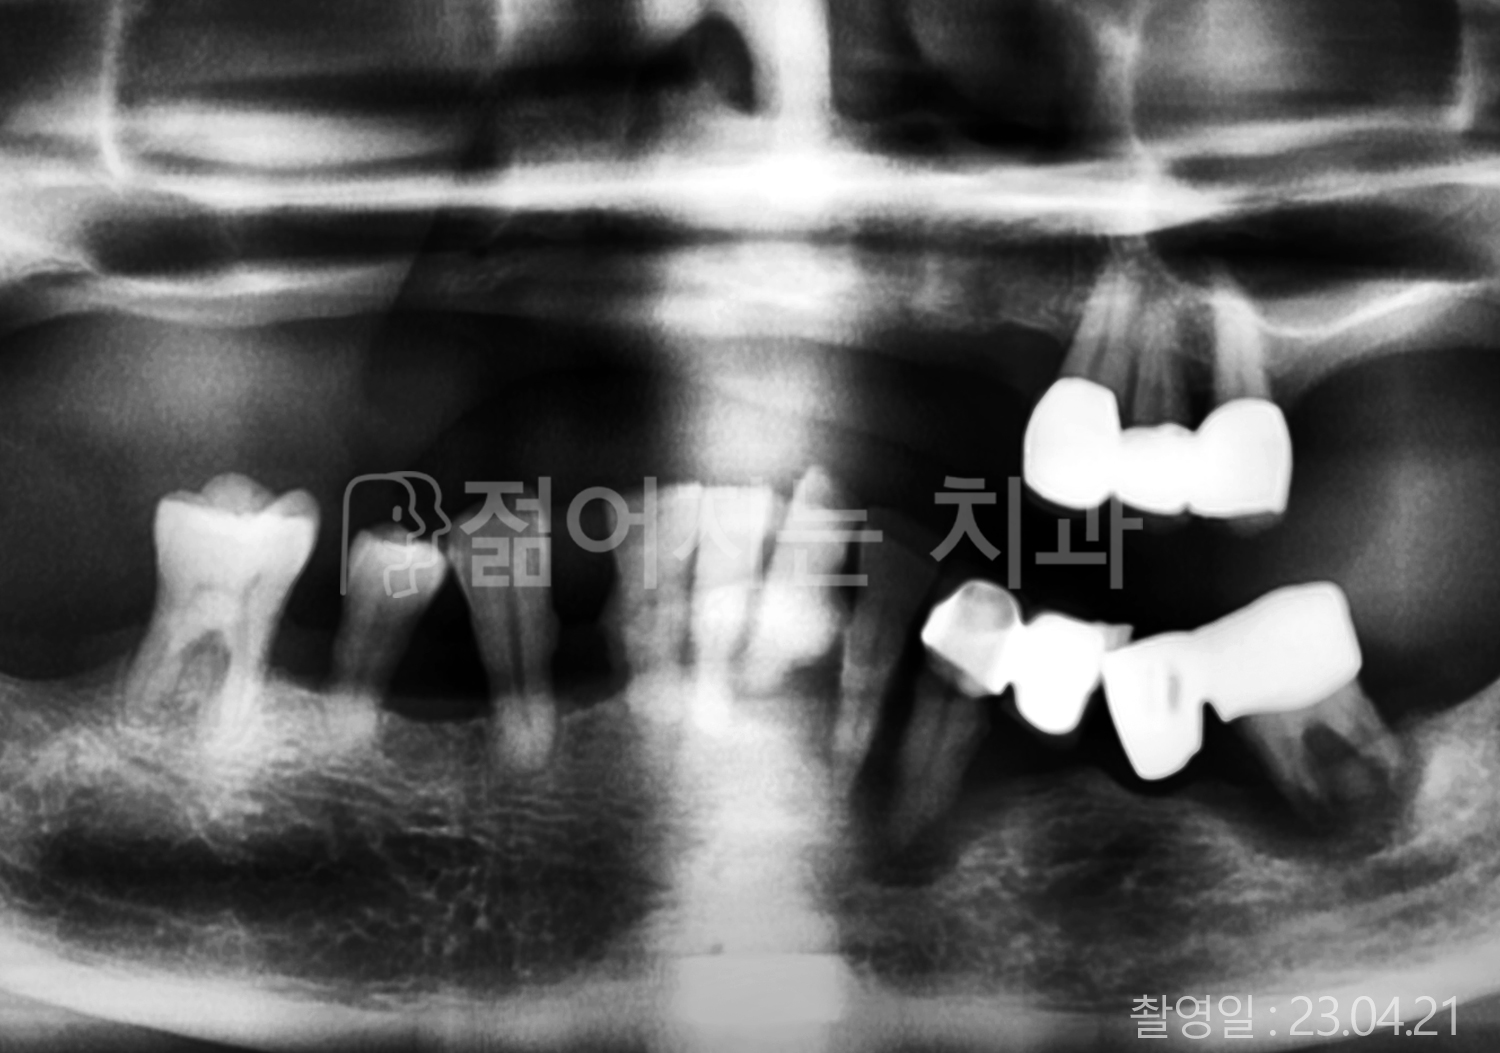

• 40대 전체치아 10개 이상 임플란트

• 70대 당뇨 전체치아 10개 이상 임플란트

• 60대 전체치아 10개 이상 임플란트

• 60대 고혈압, 당뇨, 고지혈증 전체치아 10개 이상 임플란트

• 50대 전체치아 10개 이상 임플란트

• 70대 고혈압, 당뇨 전체치아 10개 이상 임플란트

• 60대 고혈압 전체치아 10개 이상 임플란트

• 50대 고혈압, 당뇨, 고지혈증 전체치아 10개 이상 임플란트

• 60대 고혈압, 고지혈증 전체치아 10개 이상 임플란트